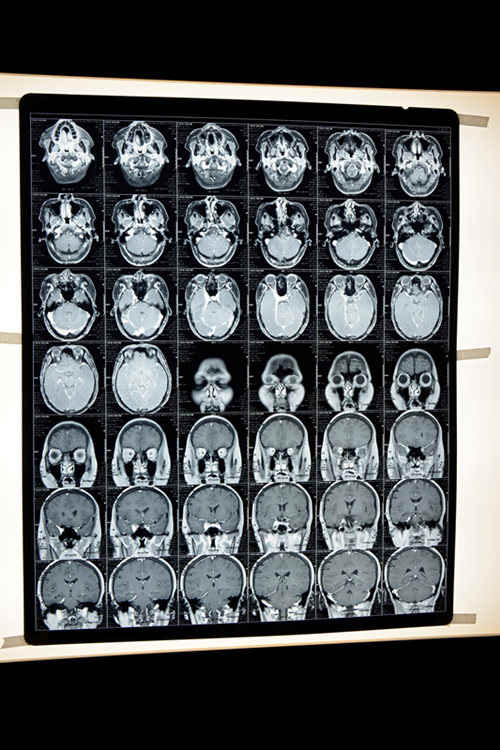

患者入院时的磁共振(MRI)影像显示:脑血管严重堵塞

余主任说,患者的血粘度太高,血液呈高凝状态,使脑血管静脉通道堵塞形成血栓,引发头痛,血栓还堵塞了视神经,造成失明。这种疾病在急性期采用西医疗法,慢性期采用中医疗法,需要灵活运用中西医结合治疗才能取得理想的治疗效果。